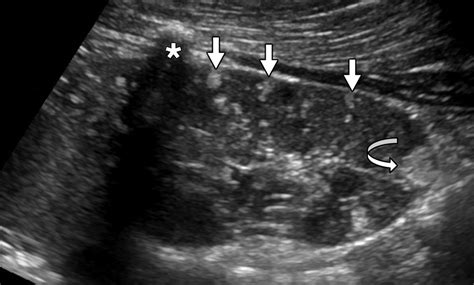

• Imaging Studies: Imaging tests such as ultrasound, CT scan, or MRI can provide detailed images of the kidney and help locate the abscess.

Imaging studies are particularly important as they can confirm the presence of an abscess and guide the treatment plan.